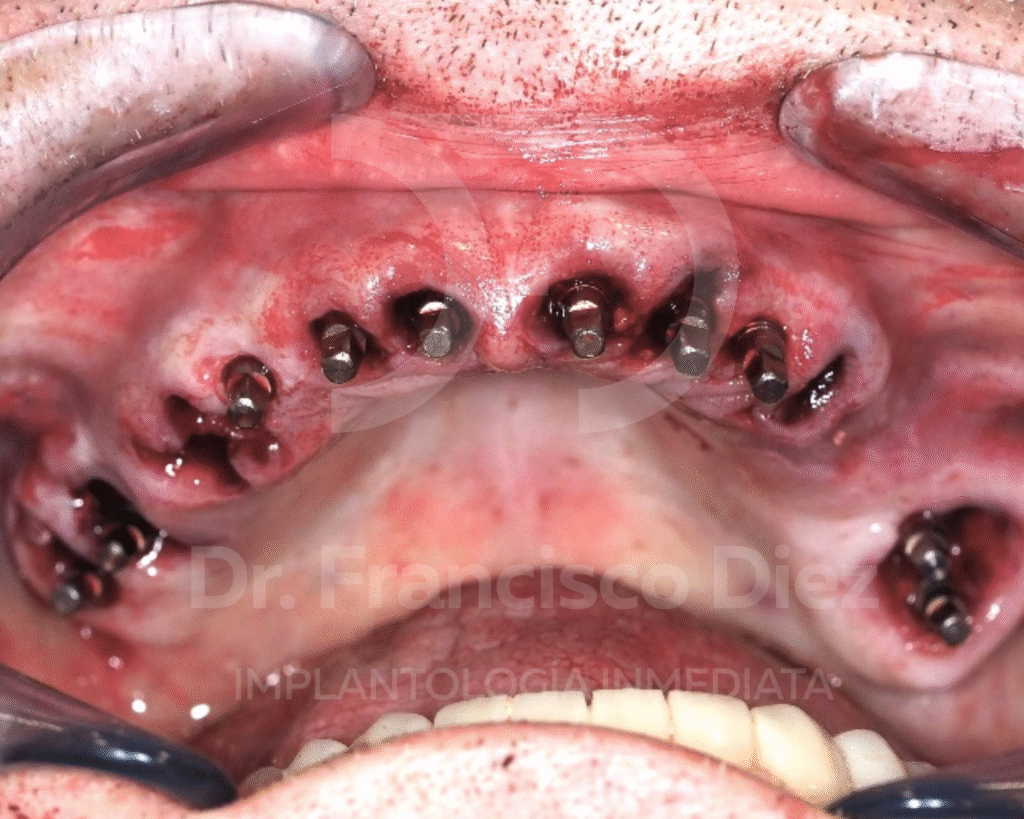

En una única intervención se procedió a la extracción de todos los dientes del maxilar superior y a la colocación inmediata de 10 implantes córticobasales BCS, anclados en hueso cortical. Esta técnica permite tratar casos con atrofia ósea severa sin necesidad de injertos, reduciendo de forma significativa la invasividad del tratamiento.